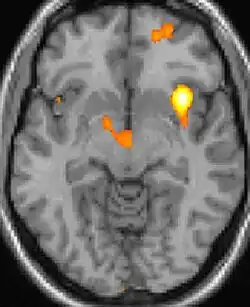

| Positron emission tomography (PET) shows brain areas being activated during pain. | ||

Positron emission tomography (PET) scans indicate the brain areas which are activated during attack only, compared to pain free periods. These pictures show brain areas that are active during pain in yellow/orange color (called "pain matrix"). The area in the center (in all three views) is activated only during cluster headaches. The bottom row voxel-based morphometry shows structural brain differences between individuals with and without CH; only a portion of the hypothalamus is different.[37]